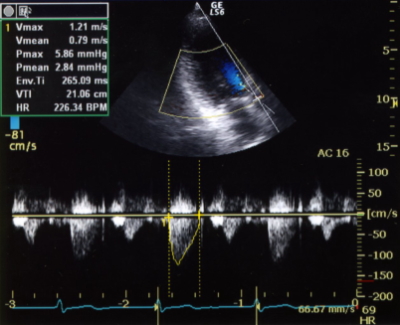

連続波ドプラ法(CWD:continuous wave doppler)は、連続的な超音波ビームを使用し、その超音波ビーム上から反射された信号のドプラシフトを解析・波形表示する方法である。ドプラシフト解析はFFTを用い、リアルタイムで画面上に血流波形を表示できる。連続波ドプラ法には距離分解能はないが、非常に高速な動きを捉える事が出来ることから、循環器領域で使用されるケースが多い。